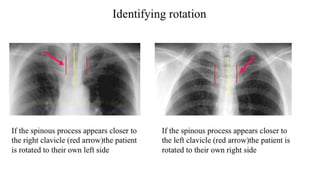

Rotation

• Patient rotation can be assessed by observing the clavicular heads

and determining whether they are equal distance from the spinous

processes of the thoracic vertebral bodies.

Rotation • Patient rotationcan be assessed by observing the clavicular heads and determining whether they are equal distance from the spinous processes of the thoracic vertebral bodies.